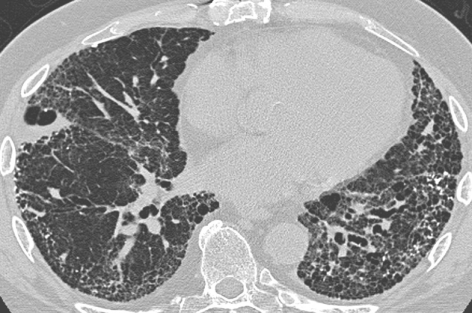

- Fleishner Society defines radiologic honeycombing as ‘clustered cystic air spaces, cysts of comparable diameters, and cyst diameters typically <10 mm surrounded by well-defined walls’. Honeycombing would present as pleural based rows of cysts stacked one upon the other, with the walls of the cysts in contact with each other (see figure below). These usually begin at the bases posteriorly but then will track anteriorly as well. You can read more on honeycombing at http://err.ersjournals.com/content/23/132/215.

- UIP pattern: This diagnosed when there are reticular opacities and honeycombing, with or without traction bronchiectasis. There should be a subpleural basal predominance with lack of the ‘inconsistent with UIP’ features. ‘Propeller blade” distribution pattern may be seen. This name is derived from the fact that the honeycombing or reticular changes move from being predominantly posterior to anterior as we move on sequential axial images from caudal to cranial. The diagnosis in these cases is unequivocally UIP.

UIP pattern. CT showing reticular opacities, traction bronchiectasis and honeycombing. (Image from Wikimedia Commons; contributed by Darel Heitkamp, MD.)